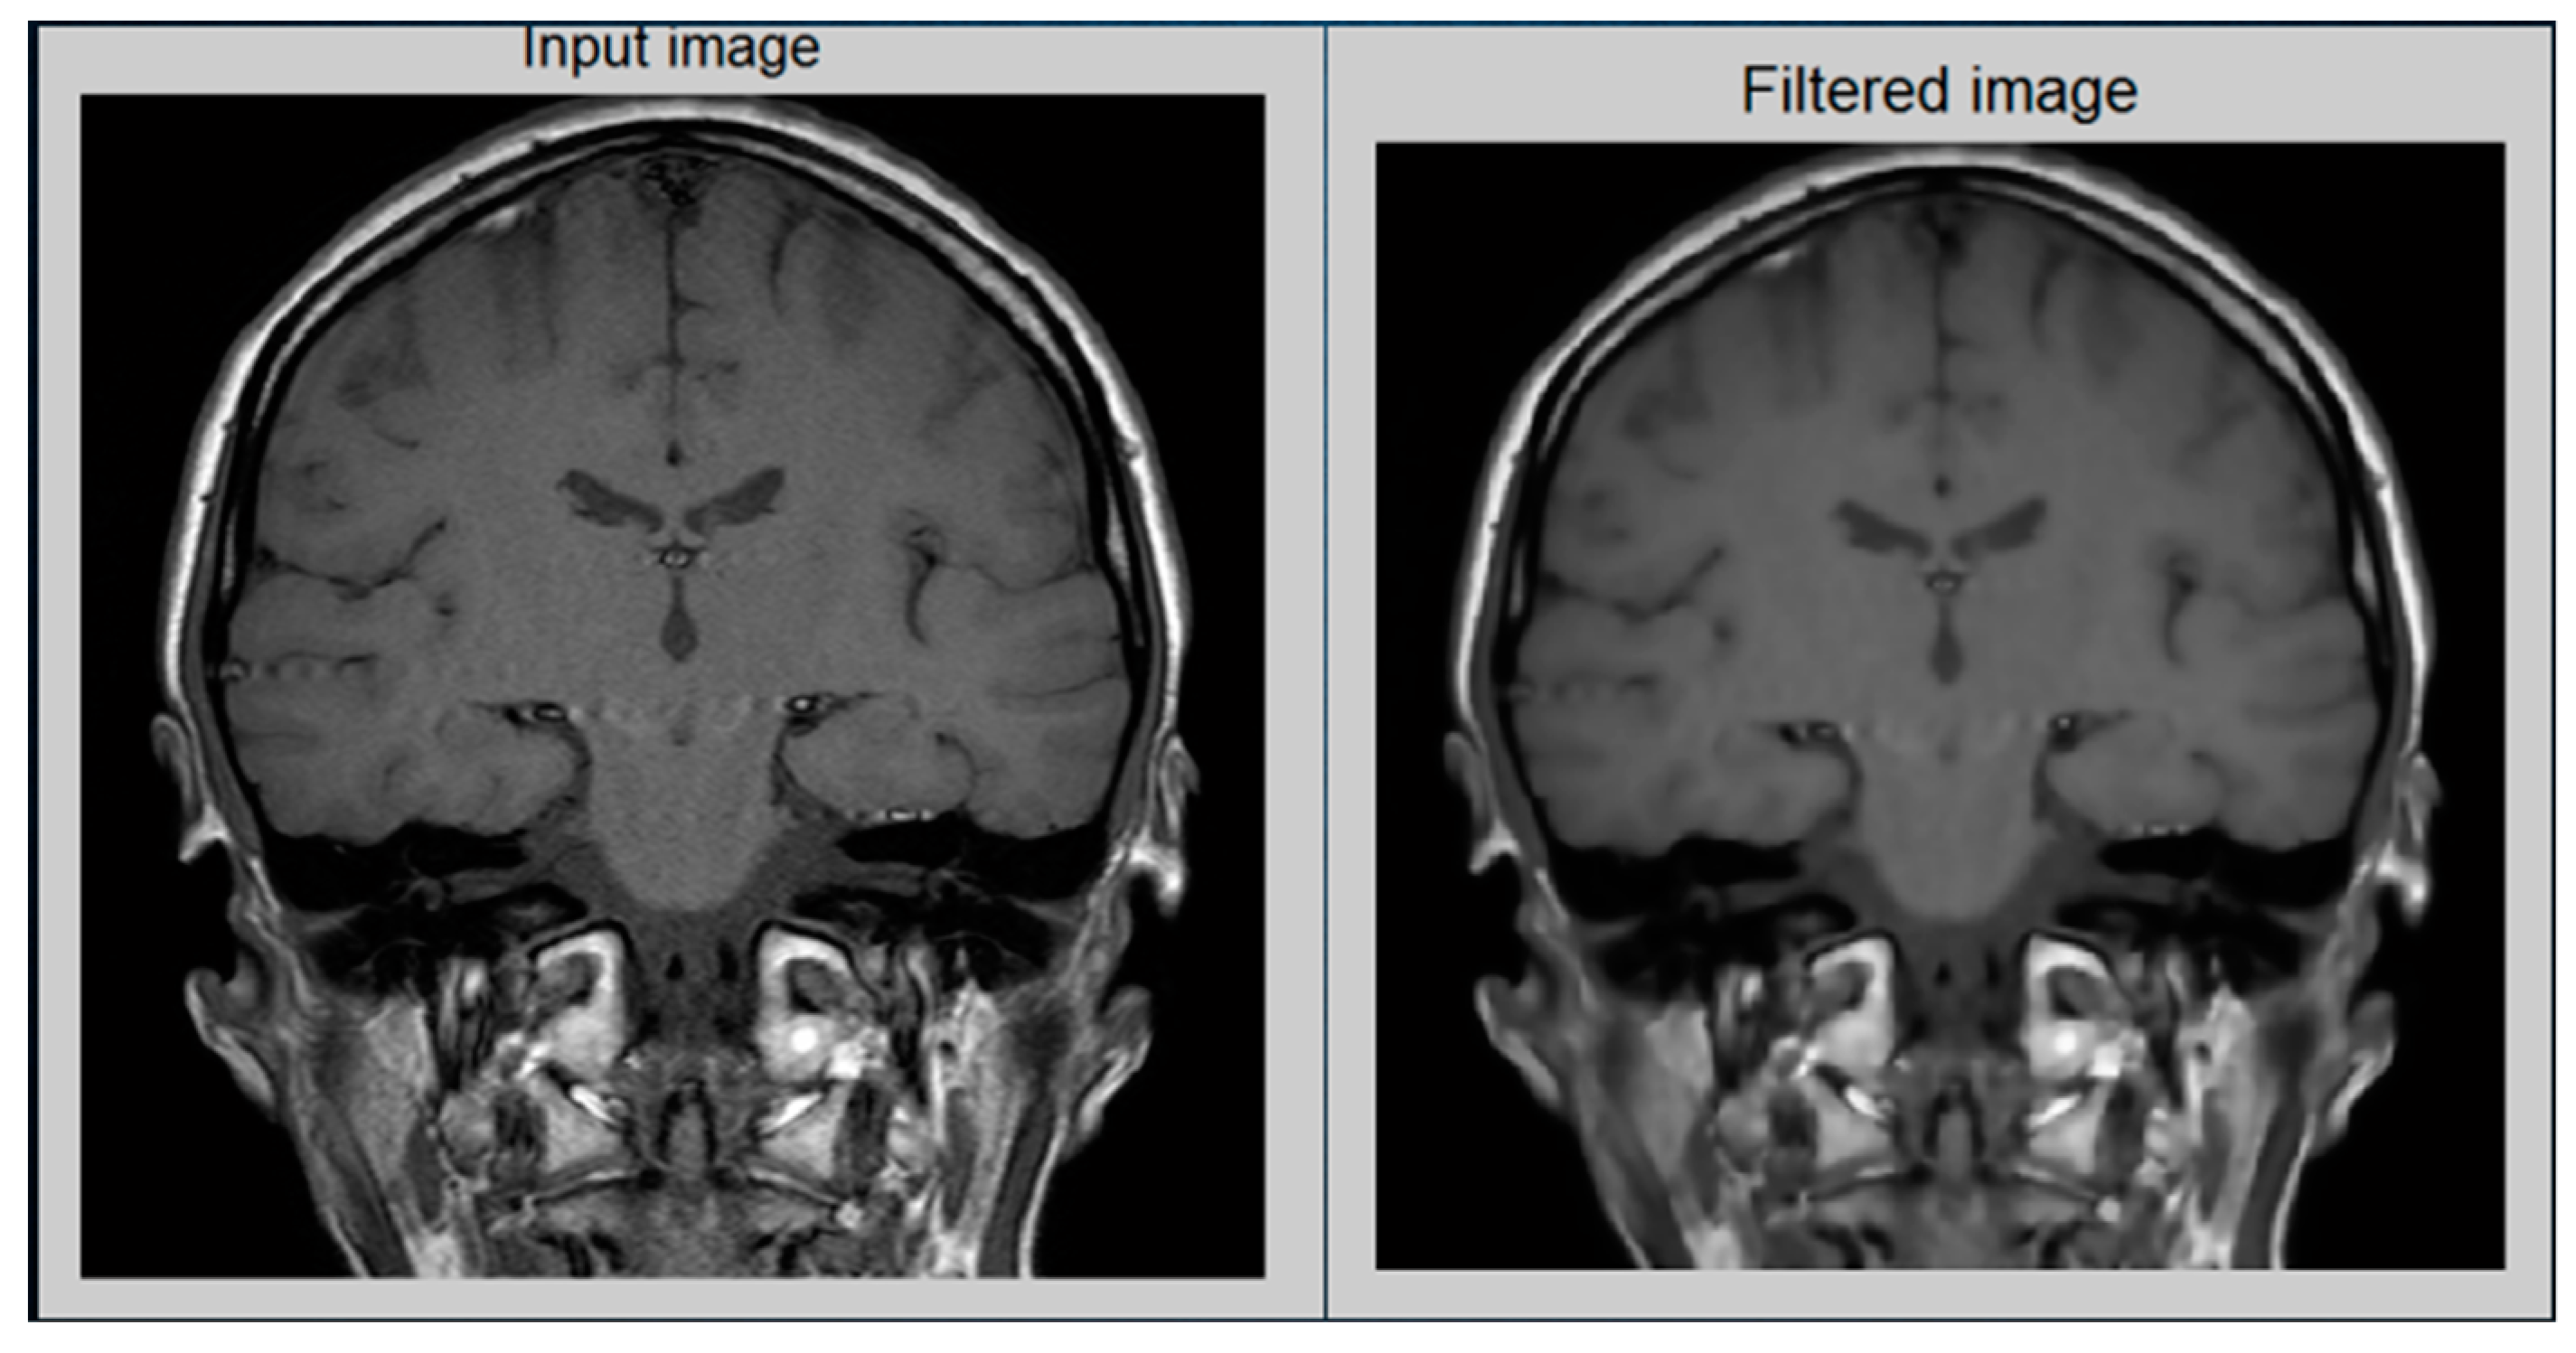

The recursive operation is completed when IE would be less than the equivalent for tolerance Tie. For this proposed approach, the test image is in Figure 6, which indicates the results.

Figure 6.

(Left): original image; (right): filtered image.